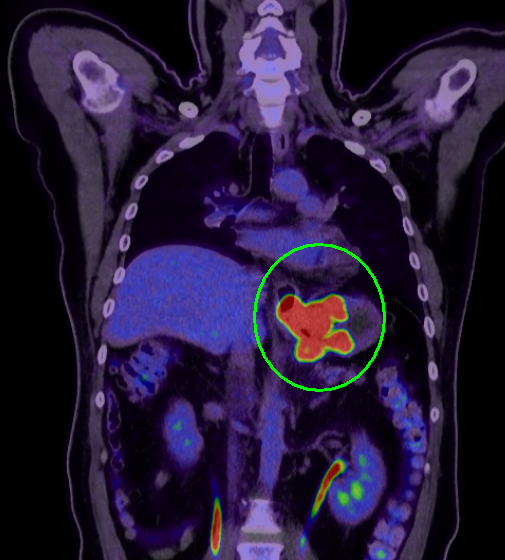

胃カメラを挿入して直接観察する内視鏡検査が行われます。進行度を判断するための検査では、造影CT検査、MRI検査、PET検査などを組み合わせて、がんの深さやリンパ節および周辺臓器への転移がないかを診断します。また、補助的に血液中の腫瘍マーカーの値を見る検査も行います。

PET/CT画像